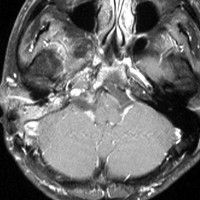

左は1991年,右は2006年のMRI画像です。15年間で腫瘍のサイズは変わっていません。

1991年に50代の女性にみつかったものでした。黄色に示したルートで摘出できないわけではありませんが,右後頭部が腫れてきたという訴えとホルネル症候,軟口蓋麻痺しかなかったので,何も治療しないでほっておきました。2016年まで25年間観察し続けました。症状の悪化は全くなく元気に暮らしておられます。グロームス腫瘍はある一定の年齢になると増大しないという性質を持っている良性腫瘍です。これを大々的な頭蓋底外科手術で摘出するするという愚を犯してはなりません。